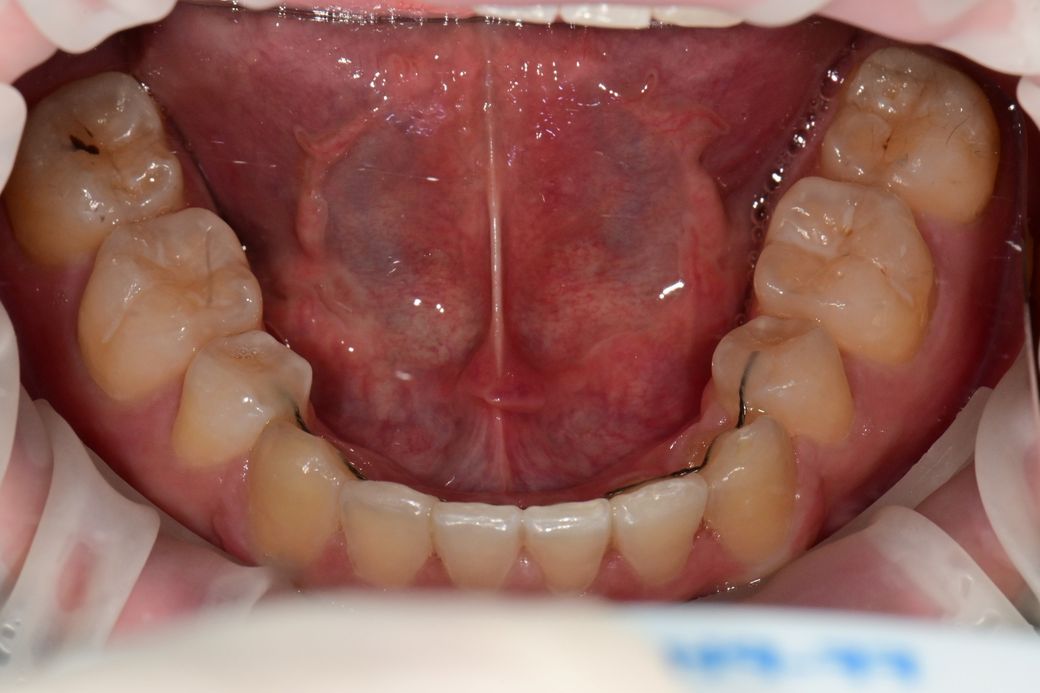

• 2번 째 사진

사진으로 봤을 경우 큰 충치가있어 보이지는 않습니다.

크게 문제가 되지 않을것으로 생각되나 자세한 확인을 위해서 치과에서 진료를 받아 보는것을 권유드립니다.

선생님마다 조금씩 견해의 차이가 나타날 수 있어보입니다. 저같은 경우엔 좀 더 지켜볼 것 같습니다.

두번째 사진이 현 상태라면 충치가 있더라도 깊은건 아닌듯 하고 치료보다는 주기적으로 체크하며 지켜보면 좋을 것 같습니다